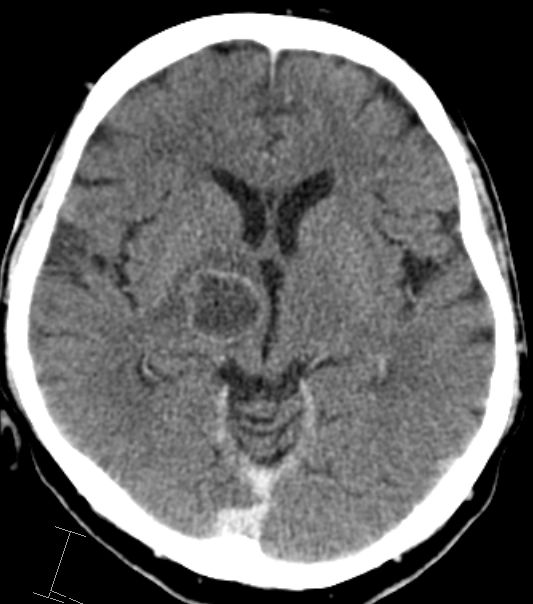

| zentrale Metastasen | 60-jähriger Mann, den vor einem Jahr ein

Plattenepithelkarzinom des linken Unterlappend cT2 pN2 Mo hatte. Nach 4x

Cisplatin-Vinorelbin und Bestrahlung vor 2 Monaten CR. Sturzes in der

Häuslichkeit eingewiesen werden. Jetzt Schwindel und zunehmende

Gangunsicherheit.

![]() |